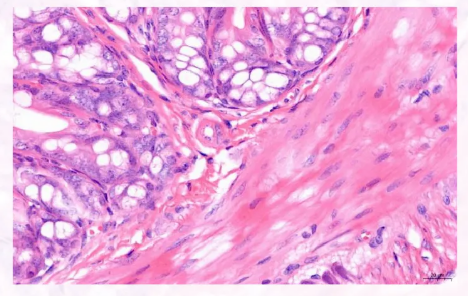

失控的炎症导致多种急性疾病的发病,如结肠炎和肝、肺和神经系统的急性损伤。急性炎症期间产生的活性氧(ROS)导致细胞膜氧化应激损伤和脂质过氧化,导致细胞膜通透性转换和DNA损伤,最终导致器官功能障碍。虽然现在已经很清楚减少或消除活性氧可以预防炎症和相关器官损伤,但传统的抗氧化剂(如维生素C、多酚、姜黄素)无法抑制由急性炎症诱导的活性氧的大量产生,这严重影响了治疗效果,限制了它们在临床上的应用。随着纳米科学和纳米技术的迅速发展,具有高效清除活性氧的纳米级抗氧化剂应运而生。一些研究报道了氧化铈纳米晶体用于治疗活性氧相关疾病,包括中风、败血症、眼表疾病、肝脏缺血再灌注损伤、急性肾损伤和阿尔茨海默病。除了强调这种材料的治疗潜力外,这些关于抗氧化剂纳米晶体在医学中的应用也面临着新挑战。例如,要确保氧化铈纳米晶体超小颗粒尺寸(最好小于5nm)以增加催化比表面积。此外,化学挑战在于增加三价铈的比例,以促进有效的抗氧化活性。生物学上的挑战是增加炎症组织中氧化铈纳米晶体的积累,因为这些外源性颗粒物质容易受到单核吞噬细胞系统(MPS)吞噬作用的快速清除。 在分析急性结肠炎和肝损伤的临床表现和小鼠模型后,炎症组织中的血流量显著升高,血管内皮破坏。根据这些病理观察和细胞膜与金属离子之间的静电相互作用,作者推测,使用细胞囊泡作为载体来改善靶向积累和模板材料来调节结晶过程可以克服抗氧化剂纳米晶体应用中的上述挑战。作者证明了氧化铈纳米晶体在纳米级红细胞(RBC)囊泡(ReV)膜上的原位生长能延长氧化铈纳米晶体在血液中的循环,并改善其在炎症组织中的蓄积。除了用作载体外,囊泡膜还可以用作模板,温和地优化纳米晶体的尺寸和Ce3+的比例,从而提高活性氧消除的效率。此外,作者通过将ReV与间充质干细胞(MSC)衍生的外泌体融合,进一步开发了该系统,为细胞囊泡提供了额外的特性,以修复高度受损的组织。上述优势已在小鼠结肠炎和肝损伤模型中得到系统验证,突出了这种新型抗氧化剂有效治疗急性炎症性疾病的潜力。